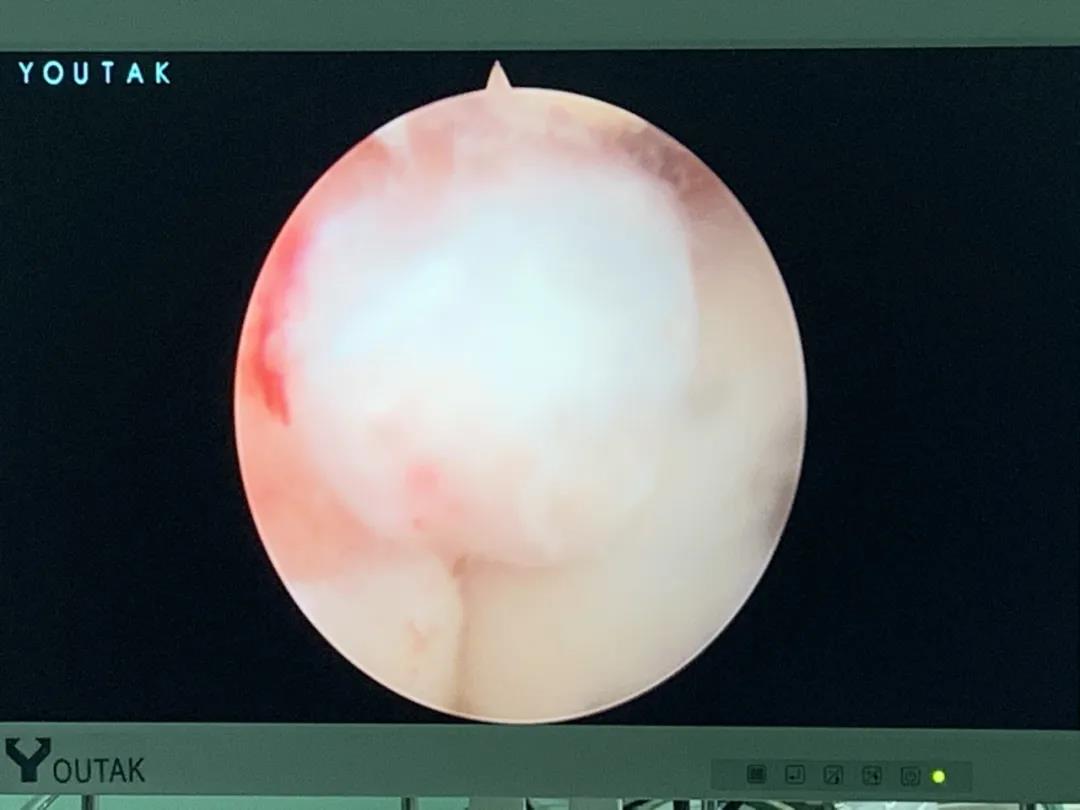

膝關(guān)節(jié)鏡

膝關(guān)節(jié)半月板損傷和前后交叉韌帶損傷是運(yùn)動損傷常見疾病,半月板損傷后不能自行愈合,盡早手術(shù)可以避免繼發(fā)關(guān)節(jié)軟骨的損傷,骨二科采用關(guān)節(jié)鏡下半月板縫合手術(shù),能少切除就少切除,能縫合盡量縫合,最大努力保留患者半月板,更好的恢復(fù)膝關(guān)節(jié)的功能。膝關(guān)節(jié)前后交叉韌帶損傷一般采用單束重建,只能恢復(fù)原來韌帶的80%的強(qiáng)度,骨二科采用雙束重建,能夠比原來的韌帶更粗更強(qiáng),為后期的功能鍛煉及恢復(fù)提供良好的基礎(chǔ)。

關(guān)節(jié)鏡下半月板縫合手術(shù)